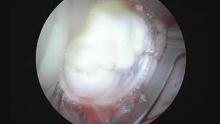

Intraoperative assessment of a competency of the repaired mitral valve before closure of the atrium is an important step in accomplishing successful mitral valve repair.

Saline test is the most simple and popular method to evaluate the repaired valve. But this kind of test in an arrested heart may not accurately reflect its function in a contractile heart and it is not always reliable because of variable physiological factors that could influence its safety.

The mitral valve is not a “static” valve because all its components are involved in its competence: the annulus, the leaflets, chordal apparatus and papillary muscles. During systole the left ventricular apex moves towards the mitral plane and papillary muscles contract and the cordae stretched. At the same time the mitral annulus reduces its surface of about 20-30% enhancing mitral competence. At the same time the evaluation of a residual insufficiency could be compromised by the anterior leaflet traction due to atrial retractor.

The natural consequence of this considerations is that a leakage test in an arrested heart in dyastole could not be considered a competence proof as in normal contractile conditions.

The cases presented in this video represent only a small cohort of patients in which a leakage test resulted detrimental for competency proof.